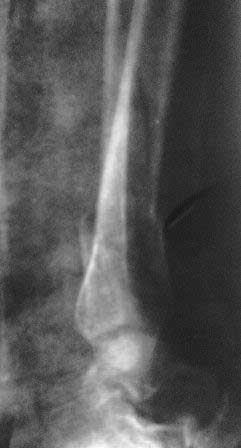

[Ortho] Вялоконсолидирующаяся перелом дистального метадиафиза костей левой голени

Пациентка 32 года, травму получила в результате ДТП, лечилась в гор.б-це №? Москвы с 19.07.по04.08.11г скелетным вытяжением, после наложена гипсовая повязка,(р-снимок 1,2.) после спадения отека гипс переведена в циркулярную, (видимо на другой вид лечения не хватило средств), гипс снят 19.11.11г(снимок-3)

.Жалобы на боли при ходьбе через несколько шагов, увеличение отека в голени и г/стопном суставе, боли ноющего и неприятного характера, хромота, при осмотре отечность голени в с-н/з и г/с суставе, при пальпации умеренная болезненность в н/з голени, подошвенное сгибание в г/с суставе ограничена и болезненна. Работа связана с ходьбой, просить помочь чтобы не потерять работу. Пока в голове только КДО аппаратом Илизарова, уважаемые коллеги  помогите советом! Доступно БИОС, пластины DCP. и прилагается последние р-снимки.